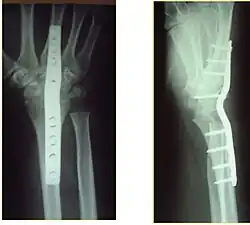

Das Verfahren der offenen Arthrodese sieht eine Resektion der knorpeligen Anteile des Gelenks vor, oft mit Entfernung des darunterliegenden Knochens, wodurch auch eine Achskorrektur erreicht werden kann. Anschließend erfolgt in der Regel eine interne Fixation mit einer Osteosynthese. Dabei können kanülierte (hohle) Schrauben (wie im Bild der Schulter-Arthrodese), K-Drähte, intramedulläre Nägel oder Platten angewandt werden. Dies hängt von der Lokalisation der Arthrodese, der Präferenz des Operateurs und der speziellen Indikation ab. Zur Verbesserung der Knochenheilung können zudem ein eigenes Knochentransplantat (Beckenkamm-Spongiosa) oder künstliche Knochenersatzmaterialien angelagert werden. Nach der Operation ist in der Regel eine mehrwöchige Ruhigstellung in einem Gipsverband oder Schiene nötig, damit eine knöcherne Durchbauung des ehemaligen Gelenkes stattfindet.